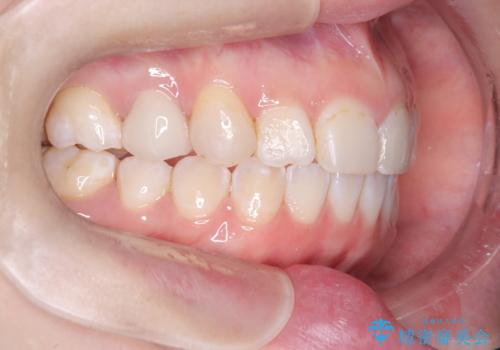

「フルリンガル矯正|アンカースクリューを活用し正中を整えた症例」

- 他院で矯正治療を受けていた患者様が、より理想的な仕上がりを求めて転院されました。主なお悩みは正中(前歯の中心)がズレていることで、歯並び全体をきれいに整えたいとのご希望でした。治療には舌側(裏側)に装置を装着するフルリンガル矯正を採用し、さらにアンカースクリューを用いて奥歯を後方へ移動(遠心移動)させることでスペースを確保し、正中を調整する計画を立てました。

矯正装置を装着し、アンカースクリューを活用しながら奥歯を少しずつ後ろへ動かし、正中を整えていきました。治療には時間がかかりましたが、計画通りに歯を移動させ、バランスの取れた歯並びへと仕上げることができました。裏側矯正のため、見た目を気にすることなく治療を進められた点も、患者様にとって大きなメリットでした。治療後は、「正中がしっかり合って、口元がスッキリした」とご満足いただきました。